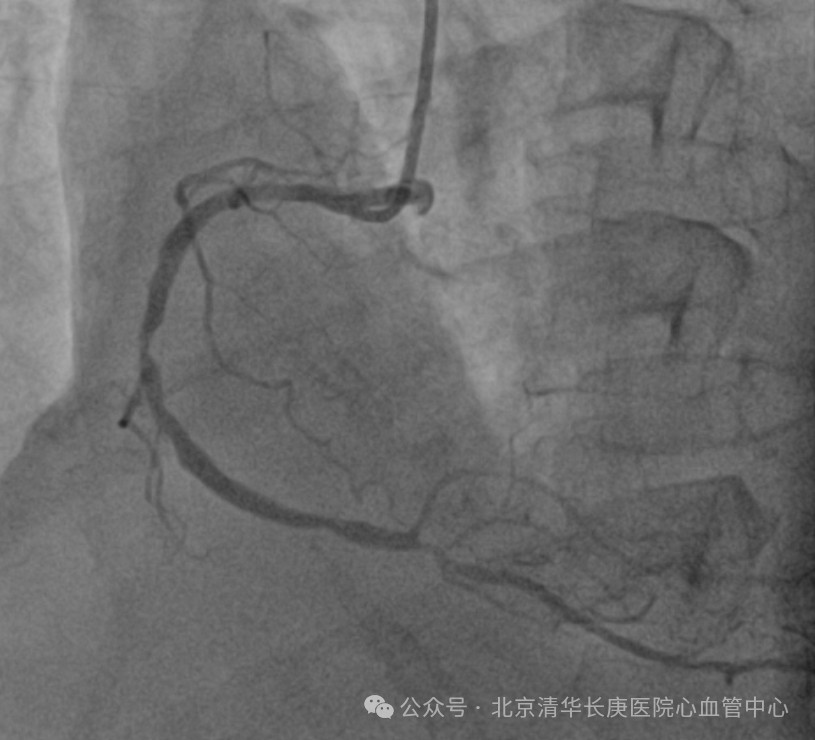

故事得从2024年元旦说起,伴随着一阵急促声,北京清华长庚医院急诊部接诊了一位突发喘憋伴一过性意识丧失的患者,急诊医师快速判断出患者存在心肌缺血及心衰表现,且合并晕厥,病情危重,遂请心血管内科急会诊。北京清华长庚医院心血管内科当天值班的佘飞主任、向伟主治医师迅速到场,详细询问后发现王阿姨患有高血压,糖尿病,高胆固醇血症多年,平素间断有胸闷症状。3个月前突发过明显胸痛1次,在家休息后缓解。此后逐渐出现活动量明显下降。当天因着急追公交车后突发喘憋伴一过性意识丧失紧急就诊。佘飞主任、向伟主治医师迅速判断出王阿姨患有冠状动脉粥样硬化性心脏病(简称冠心病),3月前突发急性心肌梗死后出现心功能不全,此次因为追公交车后出现了心衰急性发作伴晕厥。冠心病 心肌梗死非常常见,心力衰竭是心肌梗死后十分常见的并发症,严重影响患者的生活质量,也是导致反复住院甚至导致死亡的常见病因。为此,王阿姨被立即护送到心血管中心接受治疗。在佘飞主任、何榕主任及马志毅副主任医师、向伟主治医师的指导下、心血管中心医护团队为王阿姨精心制定了治疗和护理方案,超声影像团队的刘芳主任医师也为患者仔细查进行了超声心动图检查证实王阿姨的心脏出现了心肌梗死后的一系列典型改变(左心增大、室壁运动障碍、室壁瘤形成、心功能显著减低,左心室射血分数仅35%)。冠脉介入团队的耿雨主治医师随后为王阿姨进行造影检查发现王阿姨的三支冠脉均严重狭窄,其中左前降支近端100%闭塞。后续检查发现其心脏梗死面积大,冬眠心肌少。优化药物治疗后王阿姨的喘憋症状得到了显著缓解,但冠脉狭窄、心肌坏死及室壁瘤无法解决。

(患者冠脉造影)